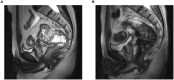

Colorectal cancer is among the most common malignancies of the gastrointestinal tract. Immune checkpoint inhibitors (ICIs) have become a key component in the treatment of locally advanced rectal cancer (LARC), offering promising therapeutic outcomes. However, ICIs can occasionally cause significant adverse effects. Herein, we report a case of rectal cancer with suspected paraneoplastic myasthenia gravis (pMG) induced by immune checkpoint inhibitors (ICIs). Unfortunately, the patient lacked anti-acetylcholine receptor (AChR)/muscle-specific kinase (MuSK) antibody testing and muscle biopsy, which precluded a definitive diagnosis of pMG. Remarkably, following surgical resection, the patient not only achieved complete tumor eradication but also experienced full remission of myasthenia gravis (MG).